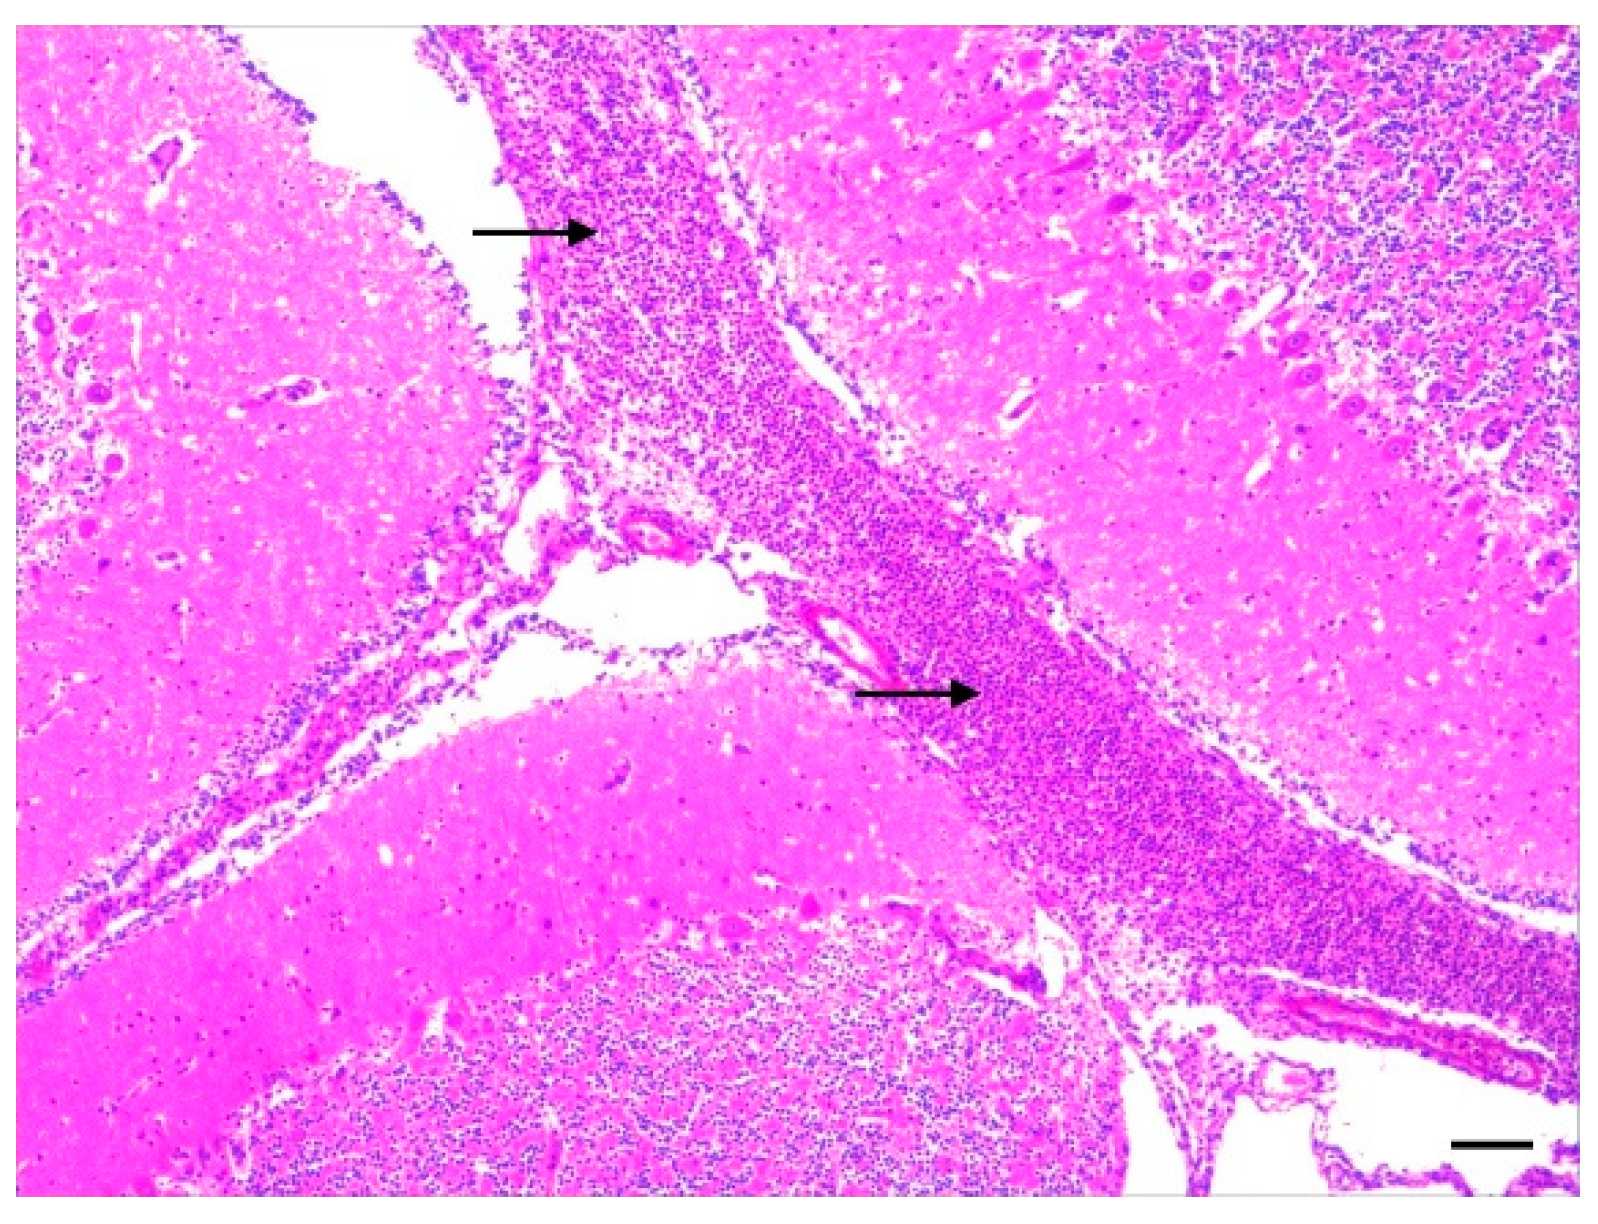

3.2. Histopathology

3.3. Bacteriology of Joint and Meningeal Swabs